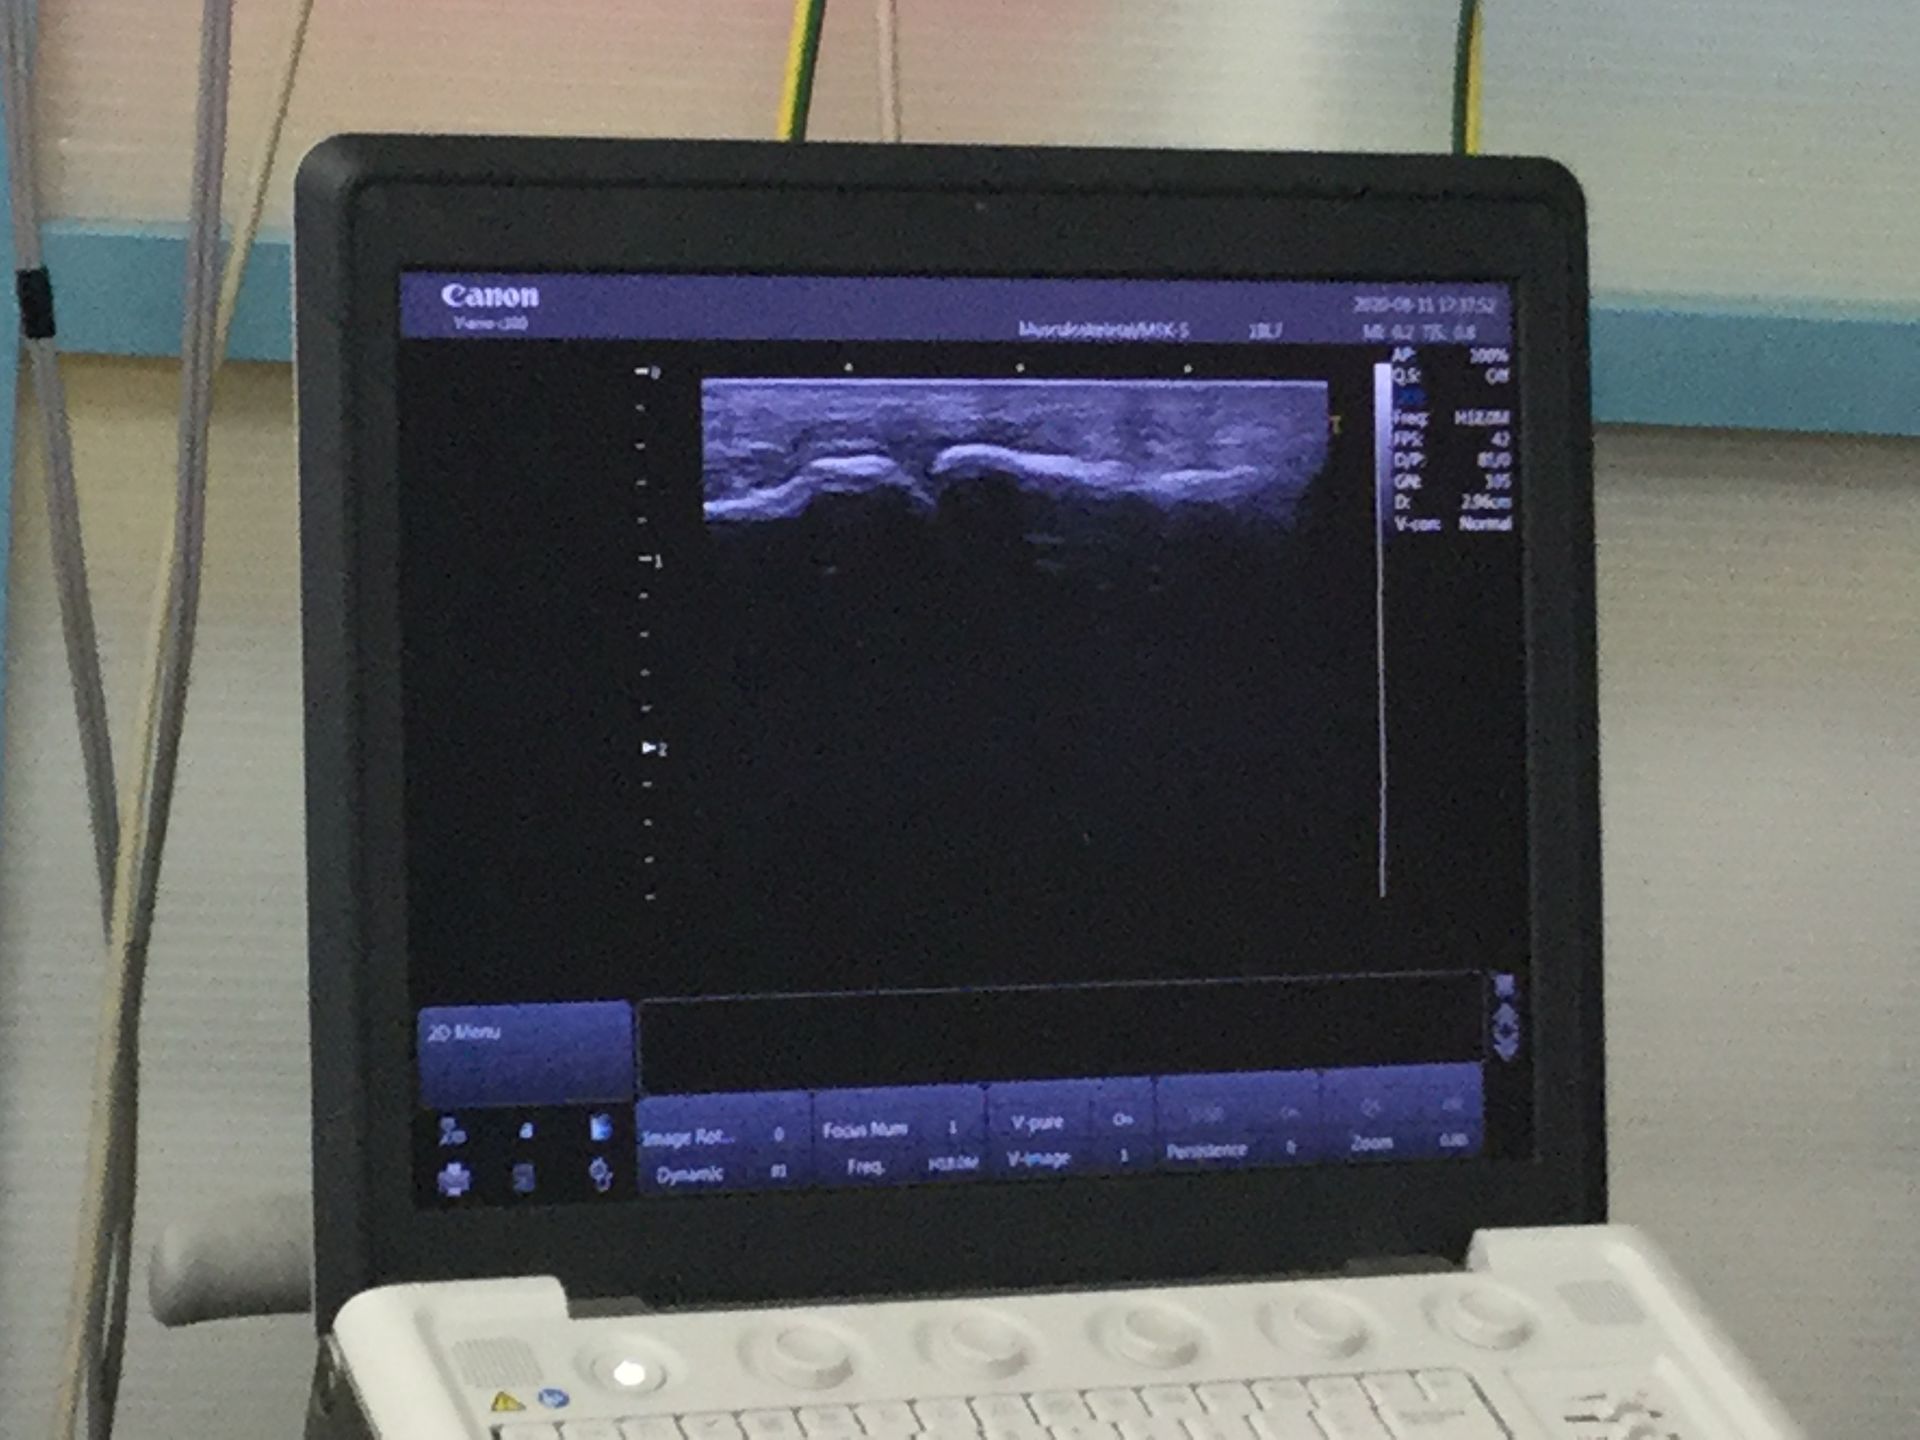

エコーで確認したところ脱臼は整復されており骨折を伴っている様子はありませんでした。

指をついた際に靭帯が引っ張られて伸びてしまってはいましたが見事な整復だったと思われます。